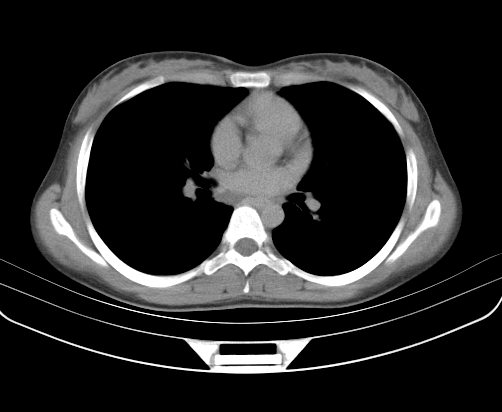

胸部